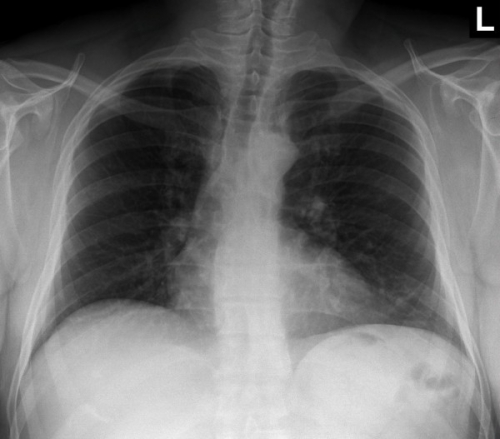

Tool to train medical student's eyes as to what a normal chest x-ray looks like, with over 500 consecutive normal images.